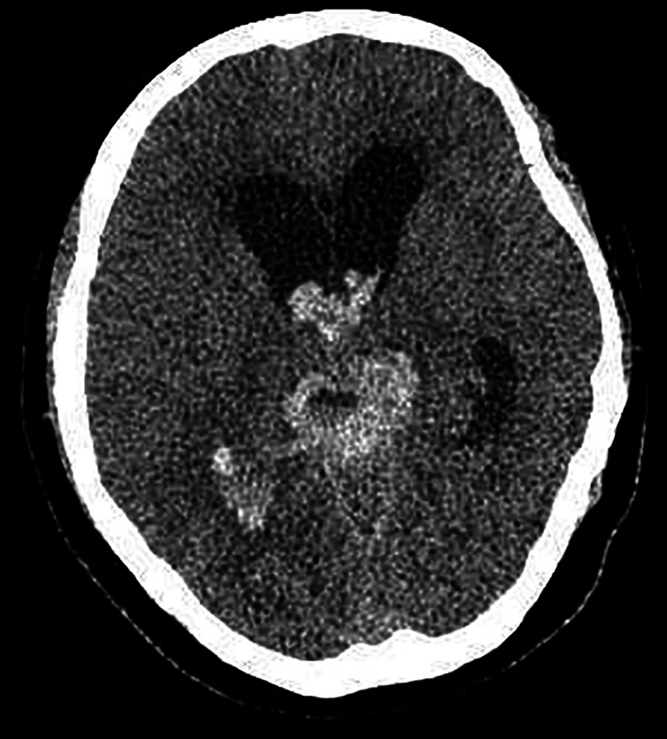

Observations: The authors present the case of a 49-year-old woman presenting with headache accompanied by nausea and vomiting. Imaging revealed a pineal tumor with subarachnoid hemorrhage. She underwent her first craniotomy at another hospital. Four months after surgery, she was sent to the authors' hospital for a second craniotomy due to recurrent cerebral hemorrhage. The postoperative pathological diagnosis was malignant melanoma in the pineal region.

Lessons: In this case, malignant melanoma in the pineal region recurred rapidly and involved the ventricles only 4 months after surgery, suggesting the necessity of close follow-up for rare tumors. In addition, diagnosing this type of tumor on preoperative imaging is challenging, and although pathological diagnosis is the gold standard, the patient in this case required repeat pathological analysis for a definitive diagnosis to be made. https://thejns.org/doi/10.3171/CASE25242.